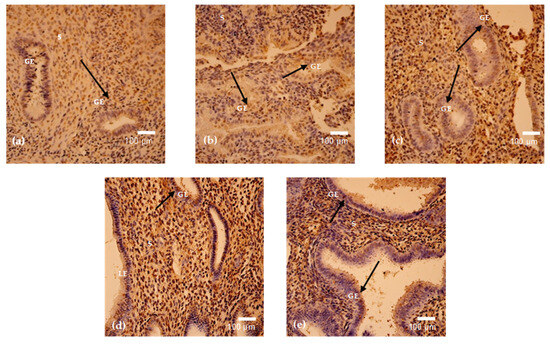

In this research, we sought to methodically examine the protective effects of Gastrodia elata extract (GEE) on liver damage induced by D-galactose (D-gal) in mice and clarify the underlying mechanisms. The chemical composition of GEE was characterized using Ultra-Performance Liquid Chromatography–Tandem Mass Spectrometry

In this research, we sought to methodically examine the protective effects of Gastrodia elata extract (GEE) on liver damage induced by D-galactose (D-gal) in mice and clarify the underlying mechanisms. The chemical composition of GEE was characterized using Ultra-Performance Liquid Chromatography–Tandem Mass Spectrometry (UPLC-MS/MS), while network pharmacology analysis was employed to predict potential molecular targets and signaling pathways. A mouse model of liver injury was established through daily intraperitoneal injection of D-gal over a 42-day period, during which the hepatoprotective efficacy of GEE was evaluated. Biochemical, histopathological, and molecular analyses were subsequently performed. UPLC-MS/MS identified ingredients such as amino acids, aromatic compounds, fatty acids, and terpenoids in GEE. A network pharmacology analysis enabled the identification of 272 common targets linked to GEE and liver damage, demonstrating notable enrichment within the phosphatidylinositol 3-kinase/protein kinase B (PI3K/Akt) signaling pathway. In vivo experiments demonstrated that GEE effectively alleviated D-gal-induced body weight loss and elevated liver index values, alleviated hepatic histological damage, and reduced serum levels of Alanine Aminotransferase (ALT), Aspartate Aminotransferase (AST), and Alkaline Phosphatase (ALP). Furthermore, GEE enhanced the activities of the antioxidant enzymes superoxide dismutase (SOD) and catalase (CAT), decreased malondialdehyde (MDA) levels, and downregulated the mRNA expression of the pro-inflammatory cytokines Interleukin-6 (IL-6), Interleukin-1 beta (IL-1β), and Tumor Necrosis Factor-alpha (TNF-α). Western blot analysis confirmed that GEE activated the PI3K/Akt pathway, as evidenced by increased ratios of phosphorylated Phosphatidylinositol 3-kinase/Phosphatidylinositol 3-kinase (p-PI3K/PI3K) and phosphorylated AKT/Protein Kinase B (p-AKT/AKT); restored the B-cell lymphoma 2-associated X protein/B-cell lymphoma-2 (Bax/Bcl-2) balance; and reduced cyclin-dependent kinase inhibitor 1 (p21) expression. The results suggest that GEE protects against D-gal-induced liver damage by reducing oxidative stress, inhibiting inflammatory responses, and modulating apoptosis through the activation of the PI3K/Akt signaling pathway, providing support for its potential use in hepatoprotection.